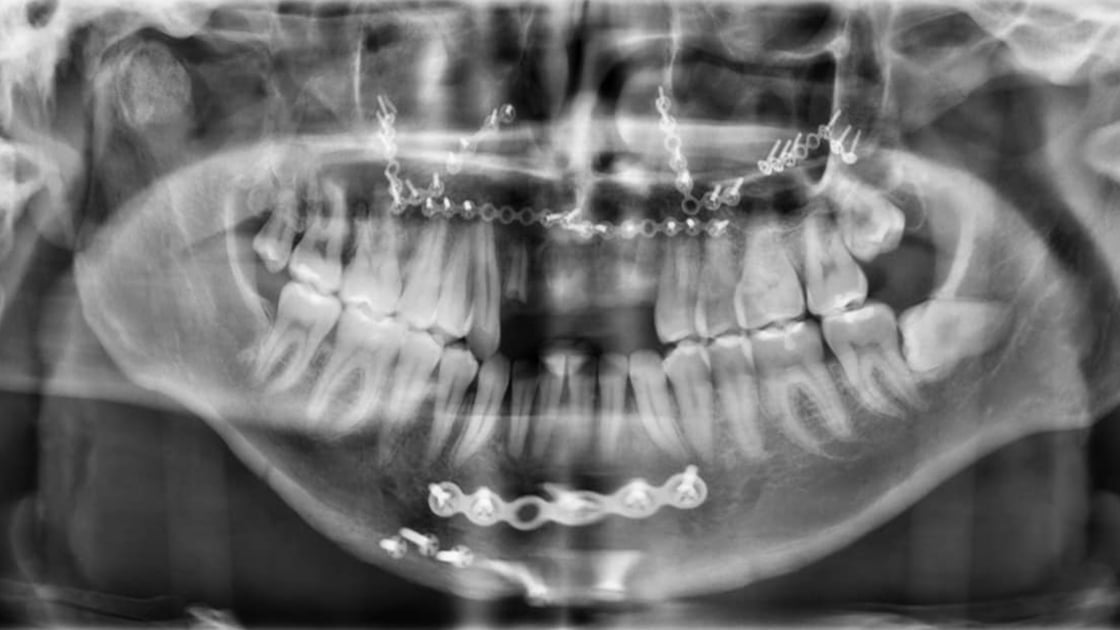

Orthognathic Surgery (Jaw Surgery)

Corrective jaw surgery can improve function and correct problems with breathing, speaking, or appearance that are caused by a poor jaw or tooth alignment.